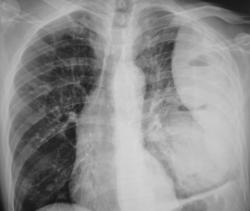

Иллюстрация 2. Слева определяется субтотальное снижение прозрачности легочного поля за счет наличия значительных размеров паракостального осумкованного выпота, имеющего чёткий и ровный контур. На фоне инфильтративно измененной легочной ткани в верхнем, среднем и нижнем легочных полях четко определяются две структуры — просветления с горизонтальными уровнями жидкости. Слева купол диафрагмы подтянут, фиксирован. Тень средостения резко смещена вправо.

Иллюстрации 3, 4. Справа определяется почти диффузное усиление, обогащение и деформация легочного рисунка, на фоне чего дифференцируются очаговоподобные тени, округлые мелкие просветления. Тень правого корня полностью нивелирована, смещенным вправо средостением.